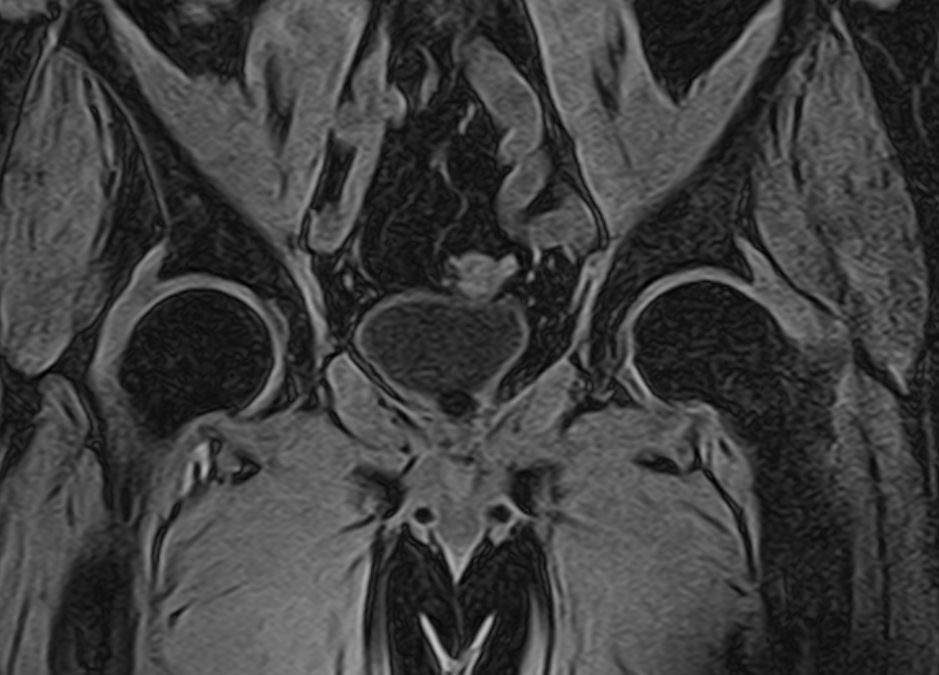

For the second patient, Hem-o-Lok clips were used for lateral dissection during laparoscopic RPE with preservation of the right NVB. In retrospective analysis of the surgery recording, it was found that one of the clips was inappropriately applied and fixed to the NVB tissue only in the area of its lock (Fig. 2). The patient complained to the urologist at the clinic of the place of residence about discomfort and pain during urination and thinning of the urine stream after seven months of surgery. The patient received

Fig. 2. Inappropriately applied clip Hem-o-Lok clip on the right NVB

conservative anti-inflammatory and antibacterial therapy without positive effect. A single bouginage had no effect. During examination, ultrasound and MRI of the bladder revealed a non-displaced concretion, which was 3 cm in diameter, fixed to the posterior wall of the urinary bladder cervix (Fig. 3). The patient underwent laser cystolithotripsy, urethrocystoscopy. After fragmentation of the stone, a Hem-o-Lok clip was detected with one end immersed in the bladder wall. The clip was clamped and removed using forceps. The postoperative period proceeded without any complications. Complaints of dysuria are completely resolved; the patient can hold urine.